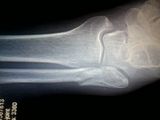

heres a pic with it evident. this was date of original injury dont think it was ortho pic. that one is next.

the next one WAS at ortho day before ORIF. IT shows bone separating kinda cool in a weird sort of way. i have it as a wallpaper on my phone lol. ppl say what happened? i show them that lol. pic to come phone copy kinda tiny. but id say it shows larger on a proper screen. but its clear. anyhoo locating dvd back in a few